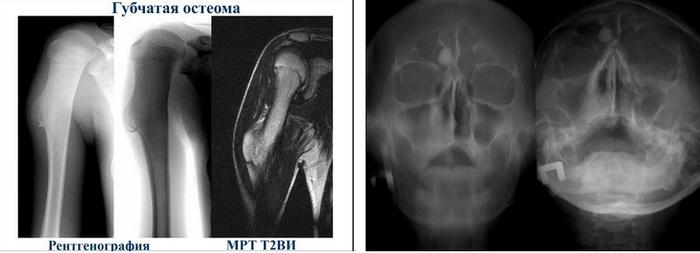

По структуре выделяются три типа остеом: компактные, губчатые и смешанные. Губчатые остеомы состоят из костных перекладин с костномозговыми пространствами между ними. Компактные остеомы имеют высокую плотность, состоят из пластиночной кости с немногочисленными узкими трубчатыми полостями и не содержат костного мозга. Смешанные остеомы сочетают в себе особенности как губчатых, так и компактных форм.

Компактные остеомы чаще всего встречаются в плоских костях (например, затылочной, в области глазницы, на стенках лобной и гайморовой пазух), в то время как губчатые остеомы обнаруживаются в длинных трубчатых костях конечностей.

Рентгенография является основным и наиболее информативным методом диагностики остеомы, на снимках опухоль выглядит как образование с высокой плотностью и четкими контурами, превышающими плотность окружающей костной ткани. Губчатая остеома на рентгеновских изображениях демонстрирует неоднородную структуру, с чередующимися зонами разрежения и уплотнения (см. изображение ниже). При малых размерах опухоли может быть назначен компьютерный томограф. При необходимости проводят гистологическое исследование, при котором выявляют характерные изменения архитектуры компактной кости, практически отсутствие каналов остеонов и сужение сосудистых каналов.